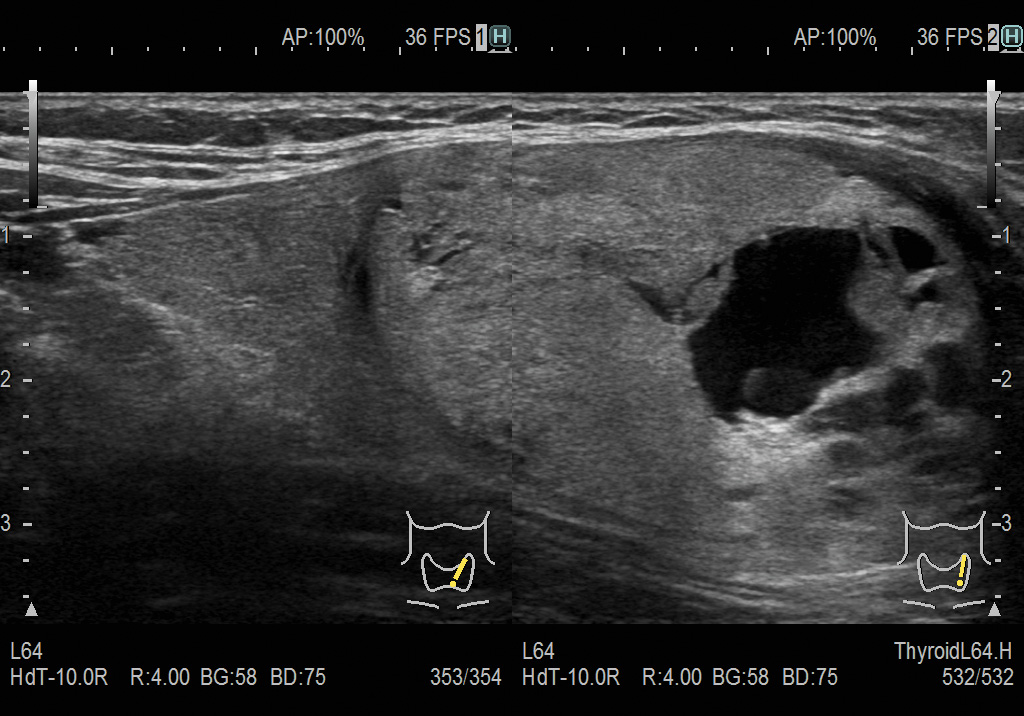

Образование в щитовидной железе. Визуализация на двойном экране в режиме eFocusing